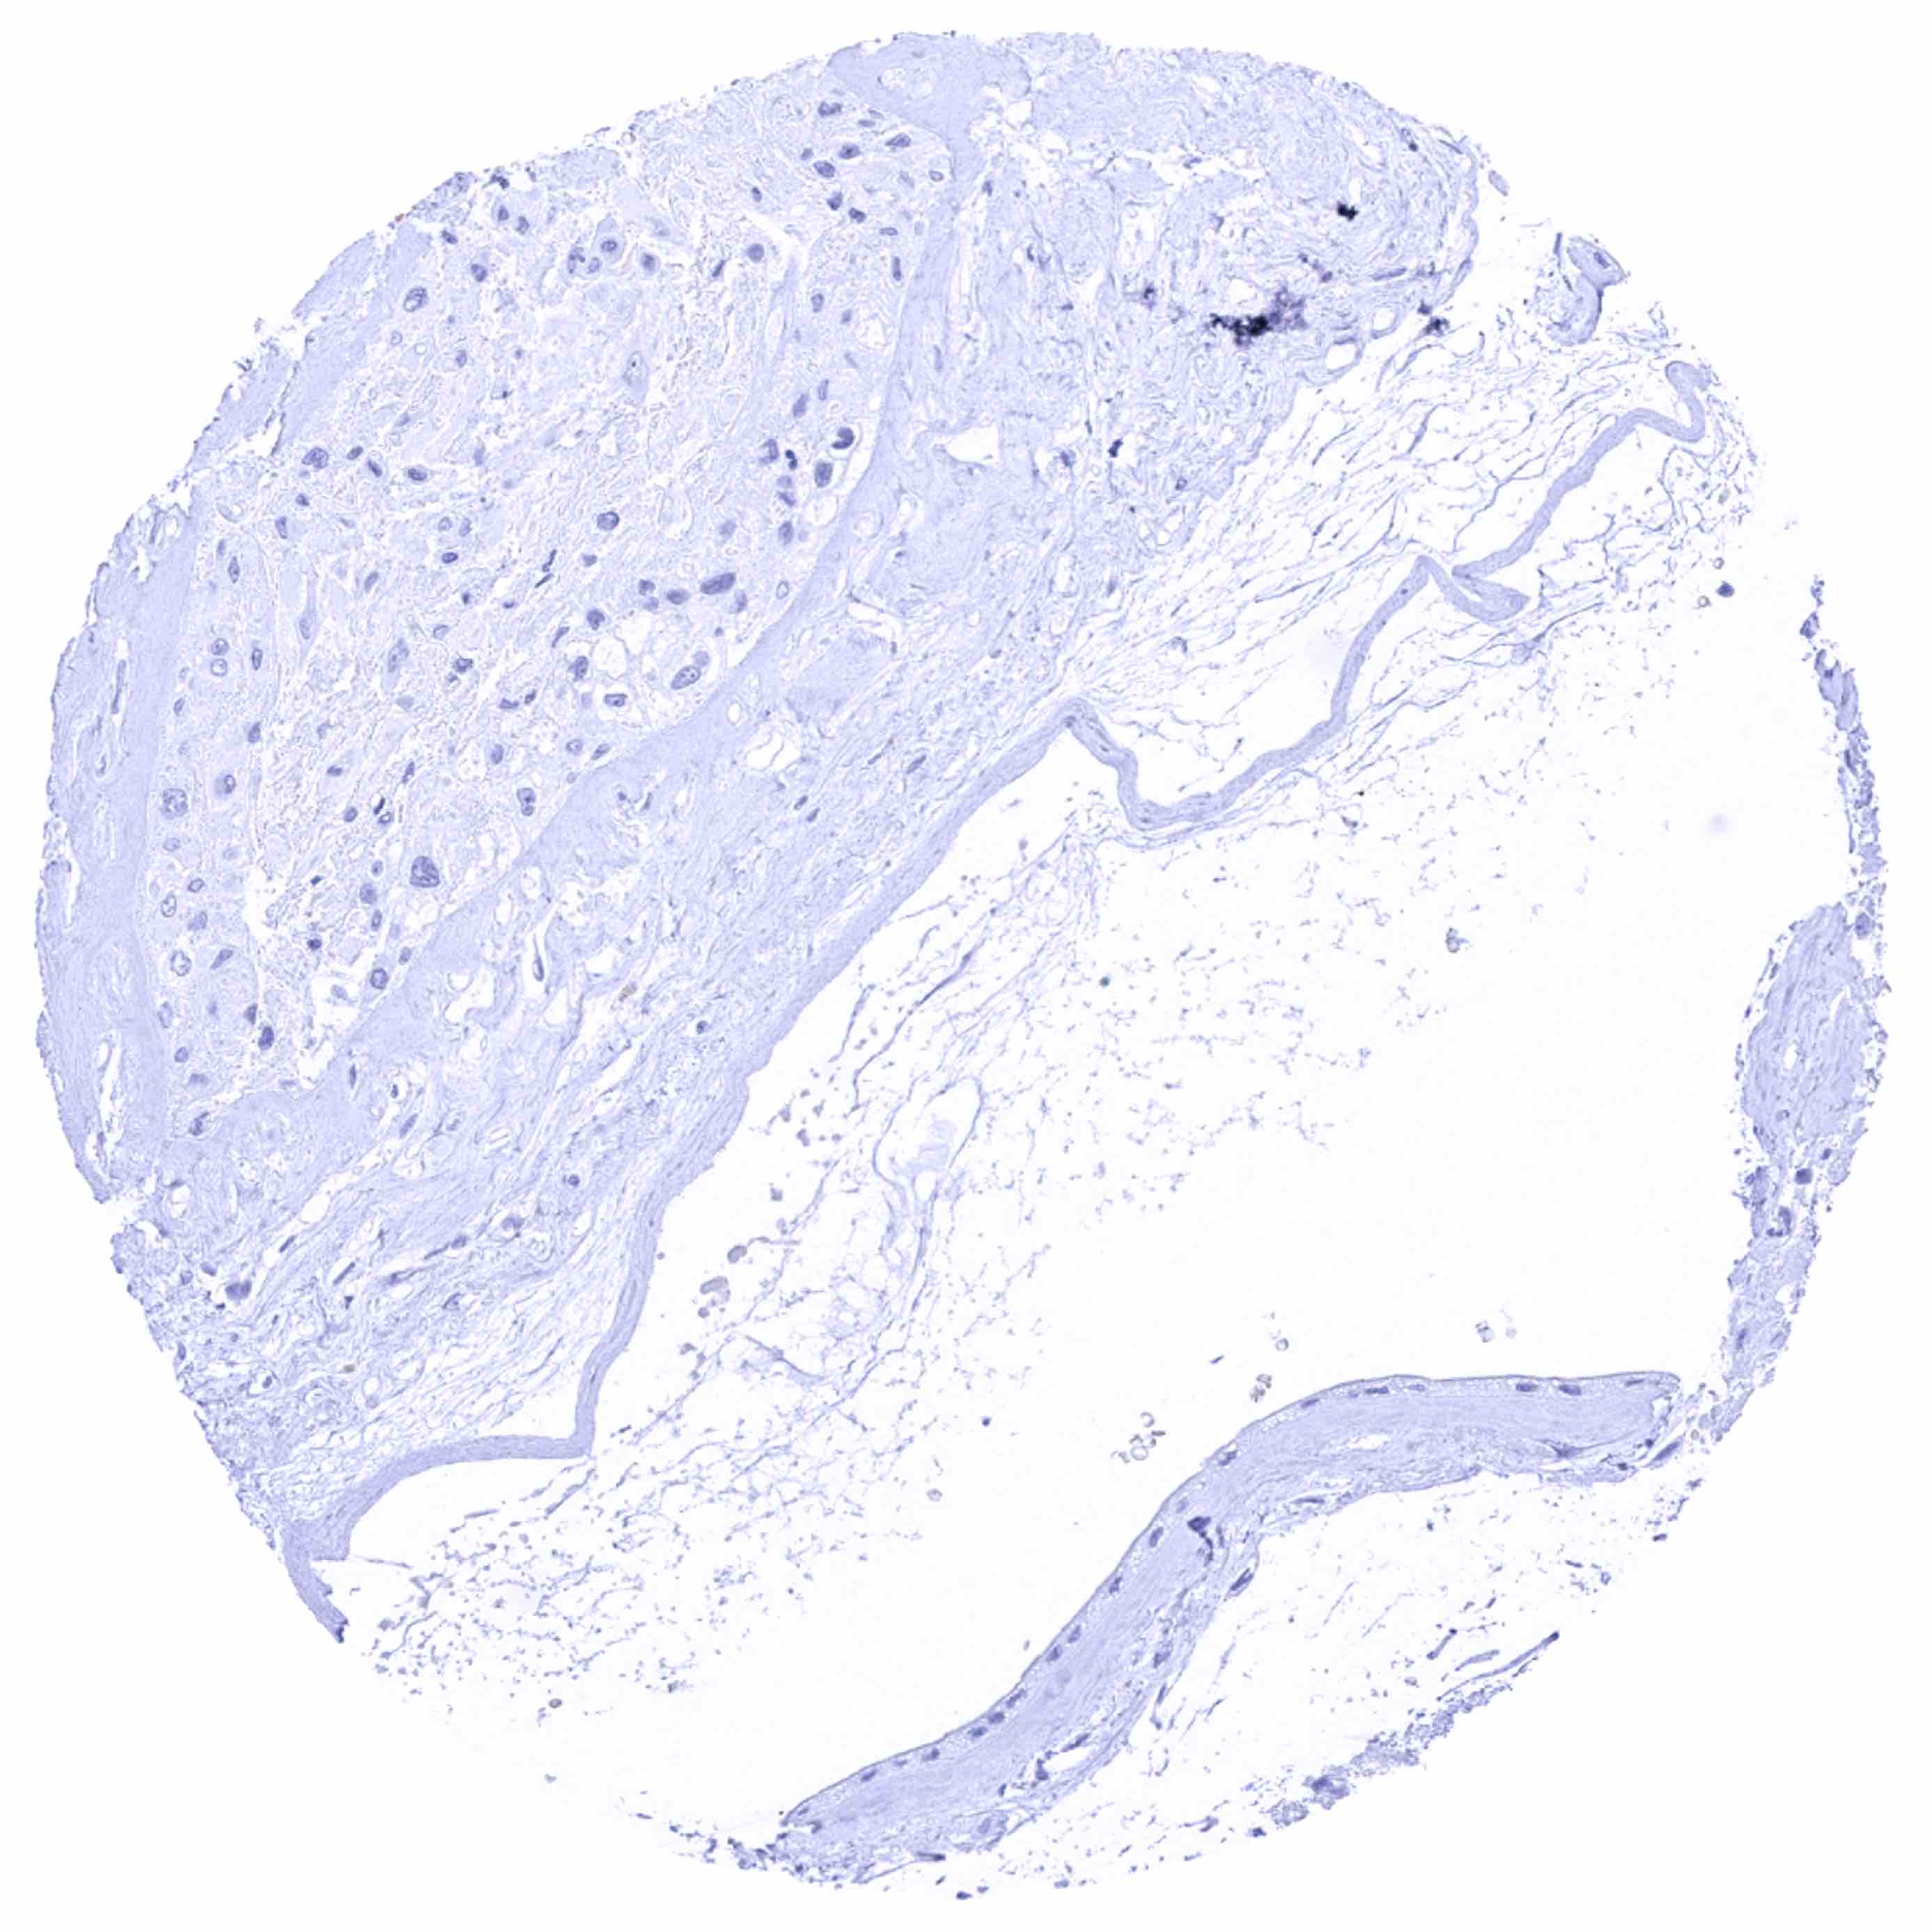

Urinary bladder, muscular wall